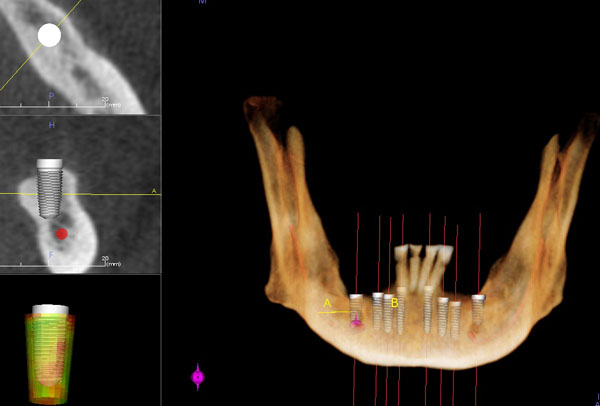

Dental CT Scan

Dental CT scan that involves 3D view of entire oral maxillofacial region (Galileos Compact, 3D Scan machine from Sirona) will also be taken of your teeth. A three-dimensional model of the mouth is a supreme assistance for implantology when planning tooth implants, but is correspondently popular for other fields of dentistry.

The 3D simulation permits doctors to:

• Detect abscess or cyst on the roots of your teeth.

• Provides cross-sections through bone matter.

• Provide panoramic x-rays that dentist use to analyze complex treatments.

• Root positions.

• Measures bone density, bone and jaw deformity and assessment of sinus..

• Bone quantity prior to orthodontic space closure.

• Oral cancer.

• CT scans are essential for the accurate placement of dental implants.